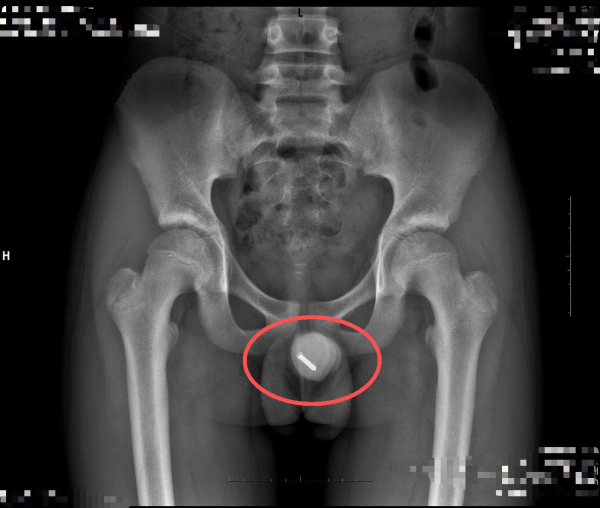

一名11岁男孩因好奇,将一根12厘米长的金属粉刺针塞入尿道,导致异物越陷越深,排尿困难,剧烈疼痛,家长紧急送医。

接诊医生介绍,这种尖锐细长的异物进入尿道,会引起剧烈疼痛和排尿困难,更危险的是,如不及时处理,异物会逆行进入膀胱。移位的异物可能刺穿薄弱的尿道黏膜,引发出血、穿孔、严重感染和尿道狭窄,甚至可能对未来的生育功能造成不可逆的损伤。

面对这一紧急情况,如何在完整取出异物的同时,最大限度地保护患儿的尿道组织,成为救治的关键。考虑到患儿仅11岁,尿道黏膜比成年人更加脆弱,手术稍有不慎就可能造成二次伤害,泌尿外科团队决定采用创伤更小、恢复更快的尿道膀胱镜下异物取出术。手术过程中,医生精准避开异物尖端卡顿的黏膜,仅用3分钟便将整根粉刺针完整取出,未造成额外损伤,患儿术后恢复良好。